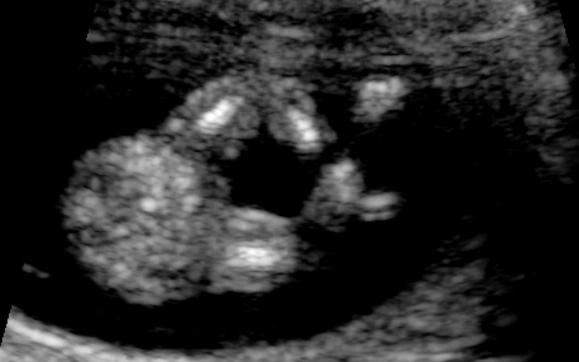

This is our first baby and I am dying to know the gender. Please see attached a few photos from our 12 week scan. What do you think - boy or girl????

Girl by NUB and skull 💝